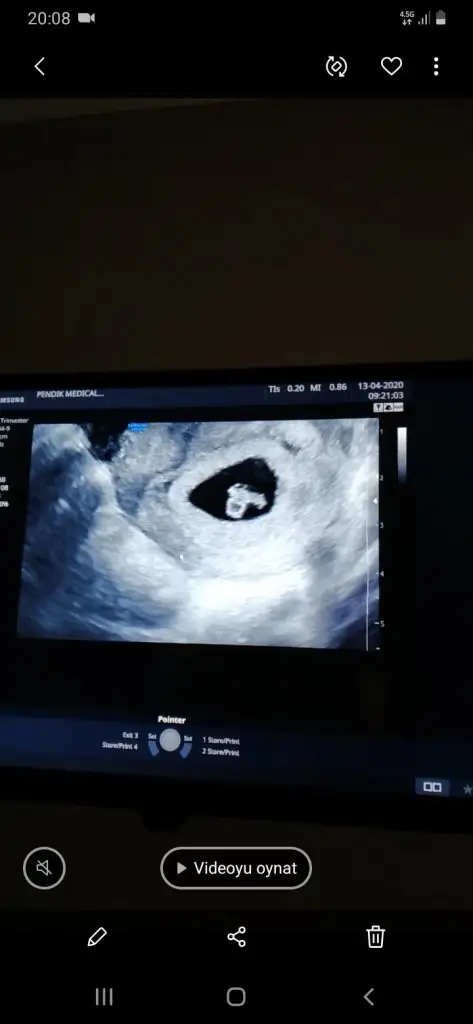

Ay ciddimisin bi yaşıma daha girdim şuna bi bakabilirmisiniz ilk çocuğumun resimleri cinsiyetini bilirse 2. Çocuğumun cinsiyetini daha erken öğrenebileceğim, çok heyecanlandım şimdidenKızlar bı arkadaş keseye göre tahmin yapıyor ve hep tutuyormuş iki oğlunu da bu şekilde cok yeniyken bile tahmin etmiş...ogullarinda kesesi hep uzunmuş muz gibi...yuvarlak ve yuvarlağa yakın olanlar hep kızdır diyor..ve bayağı emin konusuyor..benimki şişman bı fasulye gibi oo kesin kız görürsün dedi...sizlerin keselerinin şekli nasıldı ve cinsiyet neydi konusalimmi

Kesenin ucu mu yuvarlak ya da uzun olacak. 5 haftalık benim bebeğim kesenin ucunda muz gibi bir uzantı varKızlar bı arkadaş keseye göre tahmin yapıyor ve hep tutuyormuş iki oğlunu da bu şekilde cok yeniyken bile tahmin etmiş...ogullarinda kesesi hep uzunmuş muz gibi...yuvarlak ve yuvarlağa yakın olanlar hep kızdır diyor..ve bayağı emin konusuyor..benimki şişman bı fasulye gibi oo kesin kız görürsün dedi...sizlerin keselerinin şekli nasıldı ve cinsiyet neydi konusalimmi